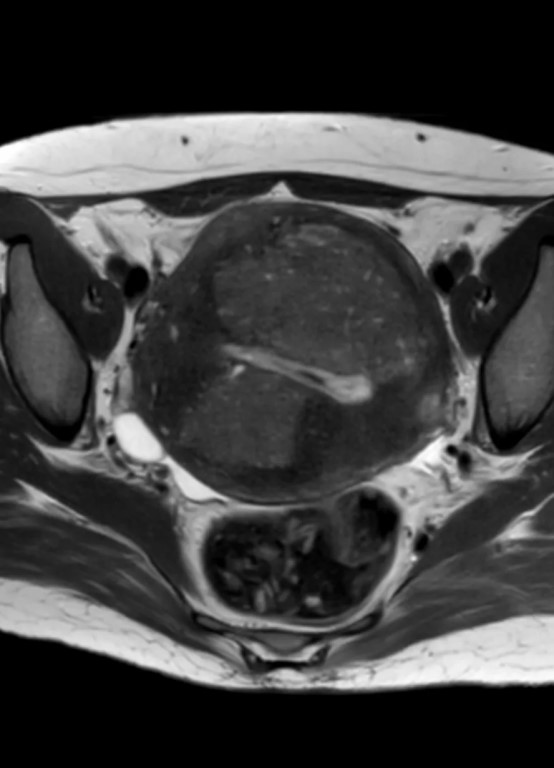

Фото Очень интересные проявления на #МРТ в матке: видно, что имеется выраженный, диффузный #аденомиоз, но какие-то узловые включения, ограничивающие диффузию и практически не накапливающие контраст. Это – результат перкутанной эмболизации, думали, что #миомы матки. Пациентка страдала маточным кровотечением. Развившиеся после процедуры участки некроза в стенках матки находятся в состоянии цитотоксического отёка и не накапливают контраст. Без знания анамнеза угадать, что это, практически, невозможно, особенно при отсутствии соответствующего опыта. Снимки и прислали с вопросом: это что такое злое в матке, но не накапливает контраст? Хорошо, что анамнез сообщили. Запись на весенние очные курсы по МРТ